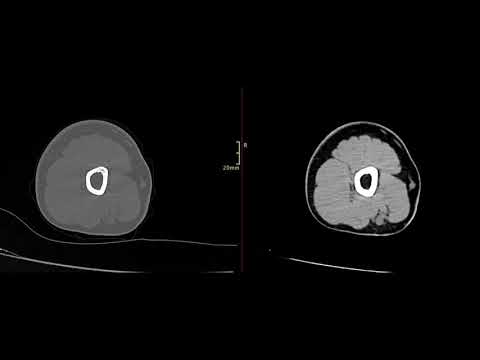

Укладка КТ шейного отдела позвоночника